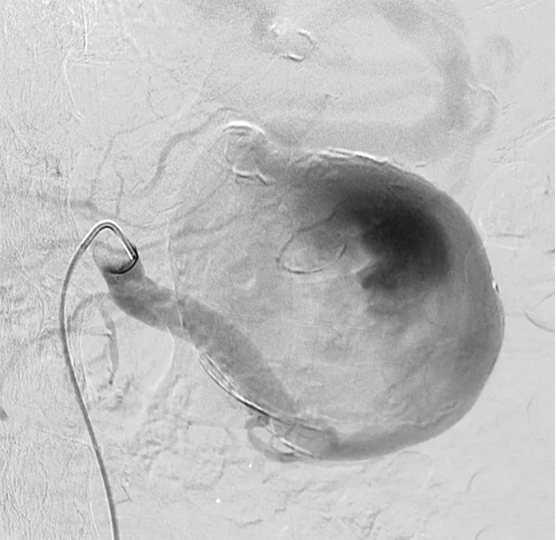

患者男,83岁,因慢性腰痛就诊。CT示7.6cm脾动脉瘤(SAA)。考虑手术风险高,决定行血管内支架移植术治疗SAA

血管造影证实saa仅在胰腺大动脉(pma)远端。用Cobra1型导管插管脾流出动脉,然后用长7Fr导套穿过SAA。多个覆膜支架在Amplatz超硬导丝上释放。血管造影显示saa排除。没有内漏。pma及脾远端动脉通畅。 |

首次修复后1年,血管造影证实支架复合物远端、第3 /4和第4 /5支架连接处存在内漏(箭头所指)。内漏通过额外的覆膜支架修复。PMA通畅(箭头所示)随访CT显示无内漏。